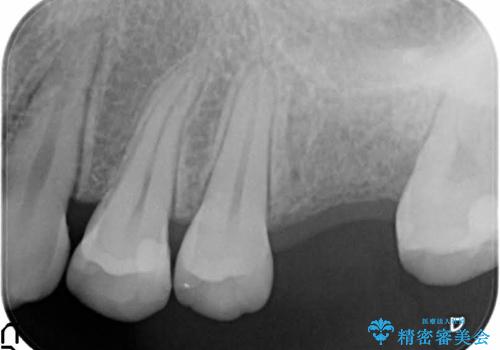

- 歯根破折を生じた奥歯を抜歯後、治癒の期間を経てインプラントを埋入

→2時手術の後、インプラントレベルの型どりにて上部構造まで完成させる